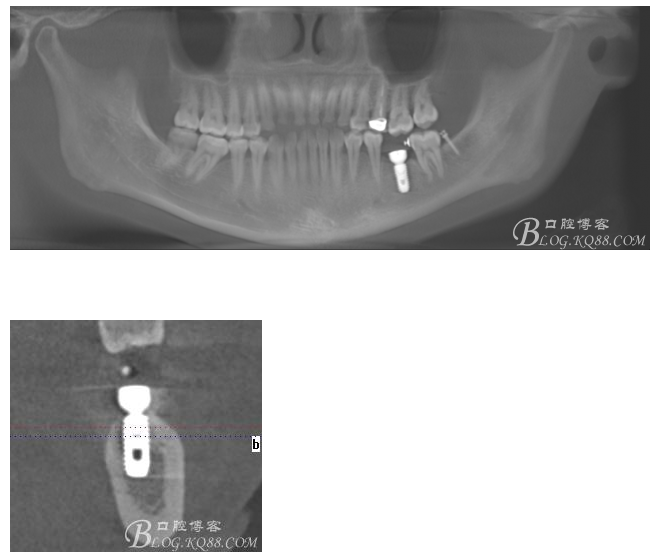

術(shù)前CT

植入5.0X10mm植體

術(shù)后CT片